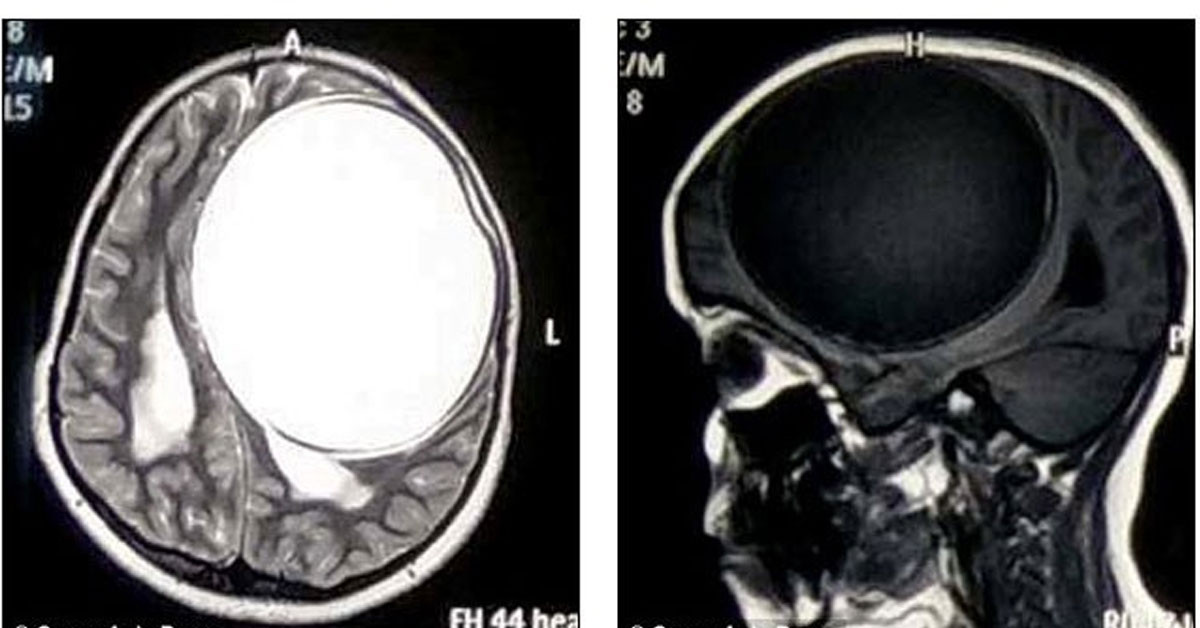

12 yaşında olan Nita Juggi isimli 12 yaşındaki küçük kız sürekli nöbet halinde ve 12 aydır vücudunun bir tarafı felçli bir şekilde yaşamını sürdürüyordu. Aile daha fazla dayanamadı ve maddi zorluklara rağmen kzılarını doktora götürdü. Doktora başvurduktan sonra yapılan çeşitli tahlillerden sonrasında küçük kızın beyninin yarısını kaplayan tenya yani bağırsak kurdu larvalarından kaynaklı merkezi sinir sisteminde sistiserkoz adı verilen bir teşhis koydu.

Küçük kızın beyninde o kadar büyük bir larva vardı ki her an patlamaya hazır bir bomba gibiydi.